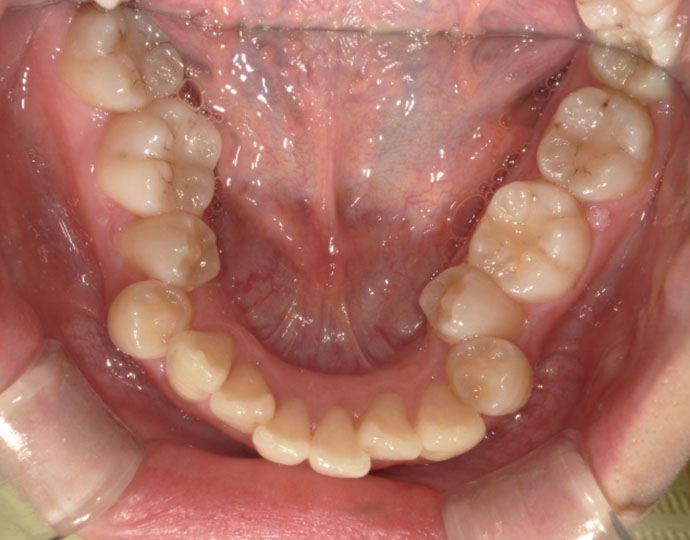

ワイヤー治療 叢生+上顎前突不正咬合 治療例

治療前

| 患者様 | 女性 19歳 |

| 主訴 | 歯並びと口元を綺麗にしたい。 |

| 診断 | 叢生歯列を伴う上顎前突不正咬合 |

| 治療方針 | 上顎左右第一小臼歯、下顎左右第二小臼歯の抜歯 |

| 治療に使用した装置 | セルフライゲーションブラケット インプラントアンカースクリュー×2 |

| 治療期間 | 2年6カ月 |

| 治療回数 | 24回 |

| 治療費(自費診療) | 880,000円(税込み) |